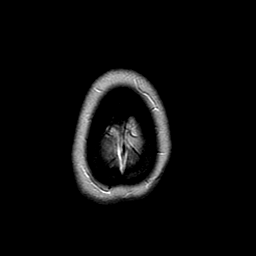

MR Study #2 -- Slice #49

[Home][Help][Clinical][Tour 1][Tour 2][Tour 3] Slice 49